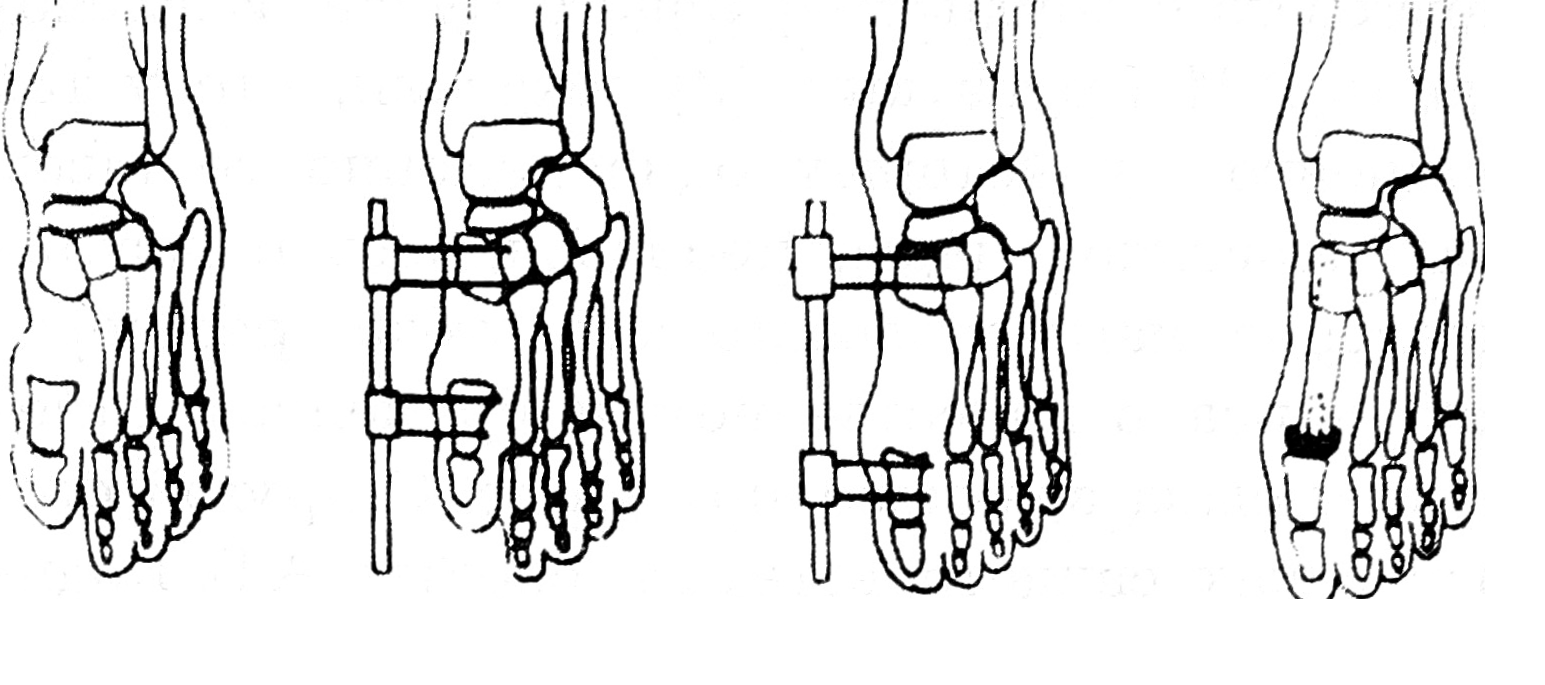

Больная К., 13 лет, поступила в ЦИТО по поводу тотального дефекта I плюсневой кости правой стопы вследствие посттравматического остеомиелита и неоднократных секвестрэктомий, с жалобами на затрудненную ходьбу и нарастающую деформацию I пальца (рис. 1). Первым этапом на I луч стопы был наложен стержневой компрессионно-дистракционный аппарат, с помощью которого создан диастаз на длину пястной кости между клиновидной костью и основной фалангой пальца (рис. 2). После этого 19.09.95 под общим обезболиванием двумя бригадами хирургов произведены замещение дефекта плюсневой кости свободным васкуляризированным малоберцовым трансплантатом, эндопротезирование плюснефалангового сустава силиконовым эндопротезом, пластика дефекта кожи полнослойным кожным трансплантатом (рис. 3). Одна бригада хирургов иссекла рубцы по внутренней поверхности стопы, выделила для наложения микрососудистых анастомозов заднюю большеберцовую артерию и сопровождающие ее вены, подготовила ложе для костного трансплантата. Вторая бригада в это время производила забор малоберцового костного трансплантата длиной 9,5 см с питающей его артерией и венами, мышечной муфтой толщиной 0,8 см. Затем костный трансплантат был адаптирован на стопе и фиксирован к соседним костям спицами Киршнера (рис. 4). Перед выполнением остеосинтеза на дистальный конец трансплантата был «надет» соответствующего размера силиконовый эндопротез, предназначенный для замещения головки плюсневой кости. Наложены микроанастомозы между артерией костного трансплантата и задней большеберцовой артерией и сопровождающими их венами. После снятия сосудистых клипсов отмечено обильное капиллярное кровотечение из мышечной муфты, свидетельствующее о хорошей проходимости сосудистых микроанастомозов и кровообращении в трансплантате. (Последнее было многократно подтверждено в разные сроки послеоперационного периода допплерографически.) На рану наложены послойные швы. Оставшийся кожный дефект размером 1,2 × 4 см закрыт полнослойным кожным аутотрансплантатом. Наложены асептическая повязка и задняя гипсовая лонгета с фиксацией стопы в положении, исключающем малейшее натяжение микрососудистых анастомозов.

Рис. 3. Схема подготовки, замещения I плюсневой кости и эндопротезирования плюснефалангового сустава.